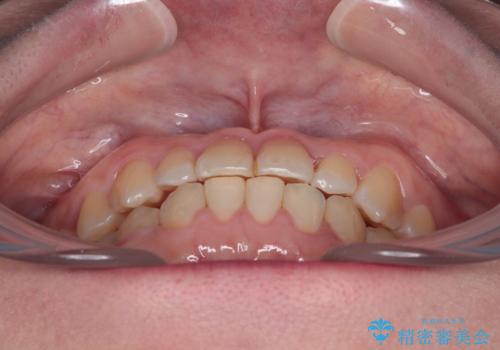

- 前歯の反対咬合を気にして来院された患者様です。

当院にて同様の咬み合わせを治療した方からのご紹介ということもあり、ご紹介者と同じワイヤー矯正で早めに治療を終えることを希望されました。

骨格的に下顎が前方に位置していましたが、歯列矯正で改善できると判断し、ワイヤー装置にて矯正治療を行うこととしました。